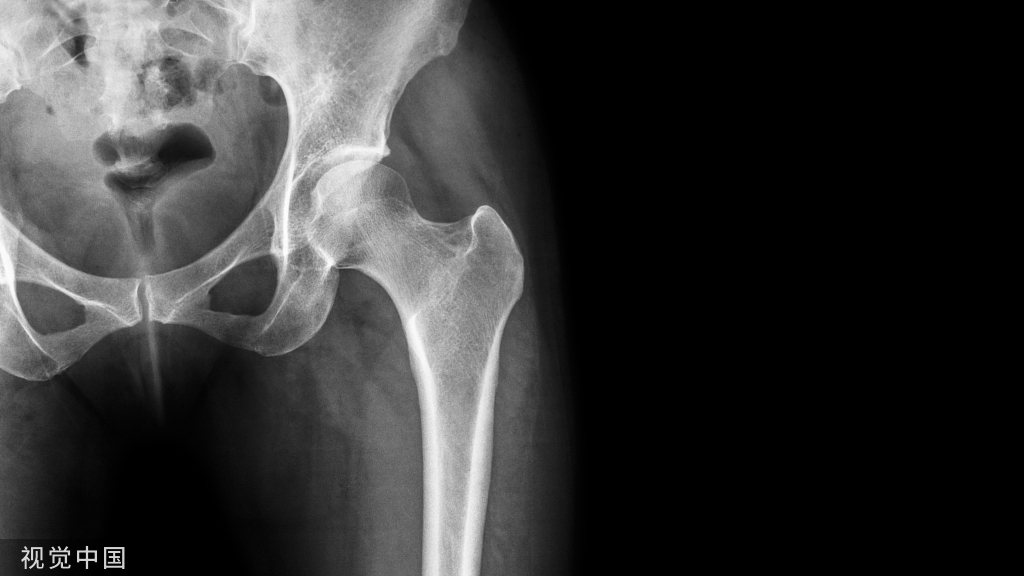

13肿瘤

• 肩关节肿瘤发病率,仅次于膝关节

• 良性骨肿瘤除非压迫皮肤或神经或恶变,都无明显疼痛

• 恶性骨肿瘤 原发、继发

原发性恶性骨肿瘤1.大多单发2.局部疼痛严重,初为间歇性,以后为持续性,非甾药不能缓解3.局部表浅静脉或毛细血管网可扩张,皮温升高,压痛明显,甚至可摸到震颤或听到杂音。4.多见于骨软骨瘤、骨肉瘤、骨巨细胞瘤

• X线:可以提示肿瘤的良恶性,甚至作出较明确的诊断

• CT、MRI:可清晰提示肿瘤范围,血运丰富与否,与邻近组织、器官的关系,有助于手术治疗